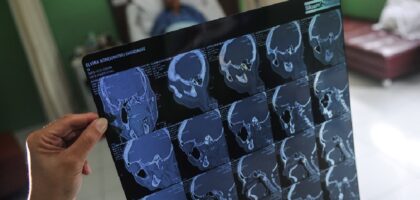

बिस्तृतमा‘ॐ अस्पतालमा मेरुदण्डको जटिल शल्यक्रिया समेत गर्छौ’

डा. गौरव राज ढकाल स्पाइन सर्जन डा. गौरव राज ढकालले दार्जिलिङबाट एसएलसीसम्मको अध्ययन गर्नुभयो । प्लस टू भारतको मसुरीबाट गरेपछि पोखराको...